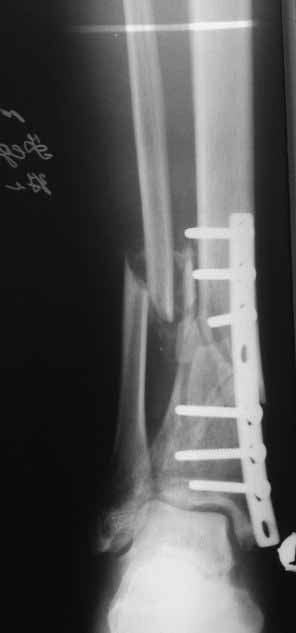

Примерная ситуация. Пациент 37 лет. Синтезировали где-то пластинкой. Попал к нам через 2 месяца.

19 апреля убрали через проколы пластину с винтами, пересекли fibula, наложили аппарат.

Немного потянули по оси, убрали вальгус, ротацию. 22 апреля (на 3-е сутки) заштифтовали окончательно. 29 апреля выписали из отделения. На все ушло 10 дней.